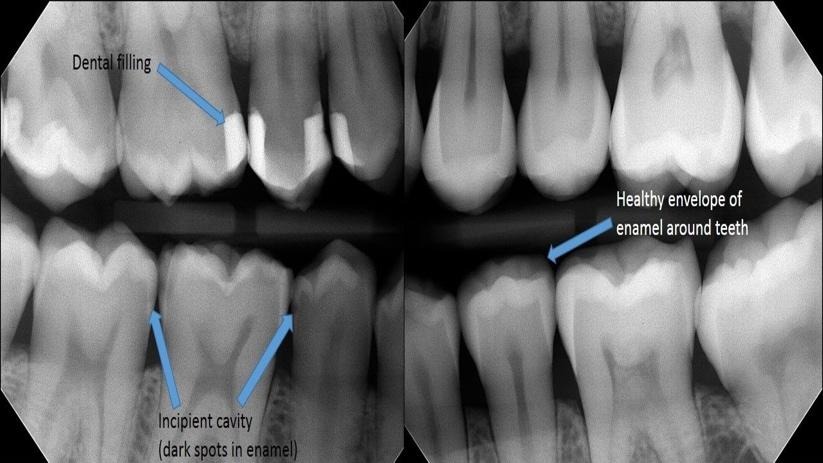

Routine dental checkups are designed to catch small issues before they become big problems. During a regular visit, your dentist and hygienist can identify early signs of cavities, gum disease, enamel wear, or infection, often before you feel any discomfort at all.

Treating a small cavity or addressing early gum inflammation is far less costly than needing a root canal, crown, periodontal treatment, or tooth replacement later. What might be a modest preventive visit today can save thousands of dollars in restorative procedures down the road.

Many dental problems don’t cause pain until they’ve progressed significantly. By the time a toothache appears, treatment is often more complex and urgent. Regular checkups help you avoid sudden dental emergencies that can disrupt your schedule, cause significant discomfort, and require immediate and often expensive care.